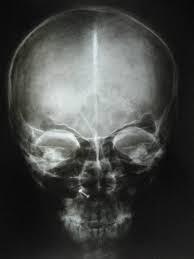

Nevoid Basal Cell Carcinoma

GORLIN SYNDROME

Chromosome 9 – PTCH gene

Characterized by:

Multiple Basal Cell Carcinoma’s - appear around puberty, where sun doesn’t shine

Odontogenci keratocysts - one of the most CONSTANT FEATURE

Calcification of Falx Cerbri

Rib abnormalities – BIFID ribs

Dangerous becuase of Basal Cell Carcinoma